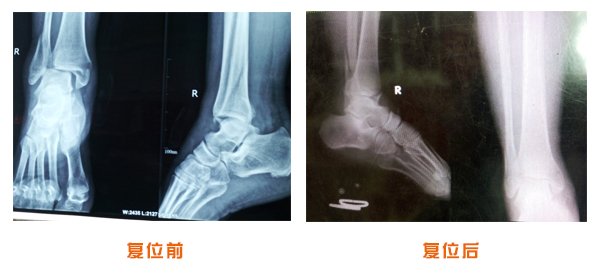

尺橈骨骨折治療前后

尺橈骨克雷氏骨折治療前后